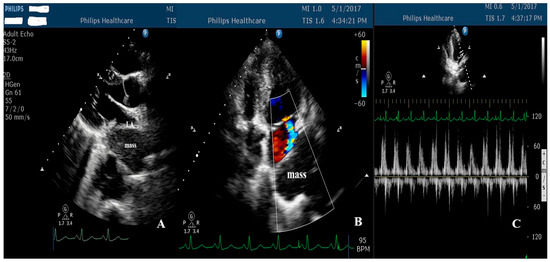

Open AccessReview

Angelina Borizanova, Elena Kinova, Semra Beyti, Todor Angelov, Plamen Getsov and Assen Goudev

Abstract

Background: Extrinsic compression of the left atrium (LA) is a rare and underrecognized condition that may result in significant hemodynamic compromise and atrial arrhythmias. The available evidence has been largely limited to isolated case reports and small case series, and clinical awareness has remained low. Methods: We performed a structured review of published case reports and case series indexed in PubMed between 2016 and 2026 describing extracardiac LA compression. A predefined and reproducible literature search strategy with explicit eligibility criteria was applied. The structured review included 22 publications reporting 23 individual cases of LA compression; in addition, two institutional cases with distinct etiologies were presented separately. Demographic characteristics, presenting symptoms, diagnostic modalities, complications, management strategies, and outcomes were synthesized descriptively. Results: The structured review identified gastroesophageal disorders, particularly hiatal hernia, as the most frequent etiology, followed by vascular, mediastinal, malignant, and musculoskeletal causes. Dyspnea was the most common presenting symptom, while hemodynamic compromise, pulmonary edema, and atrial arrhythmia represented the most frequent complications. Transthoracic echocardiography was the initial diagnostic modality in all reported cases, with computed tomography required for definitive etiological diagnosis. The two institutional cases illustrated both a common cause, hiatal hernia mimicking intracardiac mass, and a rare, aggressive malignant cause with extensive mediastinal involvement. Conclusions: Extrinsic LA compression arises from diverse extracardiac pathologies and may be clinically severe. Transthoracic echocardiography can serve as a pivotal first-line tool for early recognition and differentiation from intracardiac masses, while cross-sectional imaging is essential for etiological clarification. By integrating institutional experience with a structured synthesis of published cases, this review can provide practical insights to support timely diagnosis and management of this potentially life-threatening condition.